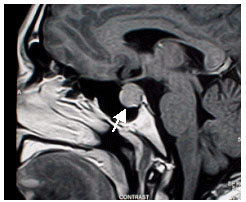

垂体功能减退性危象(垂体危象Pituitary crises)是内分泌科急危重症之一,常在应激状态下发生,其临床表现复杂多样,在非专科医院及基层医院很容易被误诊,若不及时抢救,往往危及患者生命。临床表现均有不同程度性腺功能减退表现,如性欲减退,胡须减少,体毛丧失,女性停经及乳房萎缩;同时有促甲状腺激素分泌不足的表现,如畏寒乏力、皮肤粗燥,苍白少弹性,表情淡漠,行动迟缓。发生低血压、低血糖及昏迷、体温不升,贫血,休克。血糖平均为2. 4 mmol/L,最低为0. 8mmol/L,血钠平均为122 mmol/L,最低为109 mmol/L,体温为35 ℃,表现为:混合型、水中毒型、循环衰竭型垂体危象。

垂体危象是发生在腺垂体功能减退基础之上的临床症候群。垂体激素减少后,其靶腺(甲状腺、肾上腺皮质、性腺等)发生不同程度萎缩,导致多个内分泌腺功能减退,出现相应症状体征。引起腺垂体功能减退的原因很多,最常见于垂体下丘脑附近的肿瘤、手术、放疗,颅脑外伤以及产后腺垂体坏死或萎缩。未经确诊的垂体功能减退症,在各种应激反应激治疗不当时病情发生急剧变化,出现意识模糊、昏迷或休克等危重表现。根据临床表现可分为以下几种类型:高热型、低血糖型、循环衰竭型、低温型、水中毒型以及混合型。临床上以混合型最多见,以单一类型为主要表现者临床易误诊。